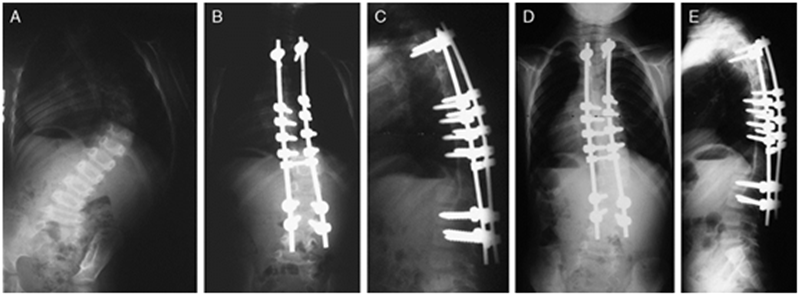

2010年,McCarthy[13]于11例动物模型中应用Shilla技术治疗,结果显示:平均的生长长度为48mm,解剖仅观察到微小的磨损但无断钉断棒等;McCarthy[14]于2014年又报道了38例行Shilla技术治疗的患者,术后3个月予以支具保护,随访2年以上(图 3),术前Cobb角平均为70.5°,术后6周为27°;2年随访示肺容量改善13%,躯干高度(C7-S1)增长12%,出现了3例棒相关并发症,2例感染。

图7 McCarthy等[14]报道了38例行Shilla技术治疗的患者,随访2年以上。A:3岁婴儿特发性脊柱侧凸患儿术前正位X片;B和C为术后3月影像资料;D和E为术后2年正侧位X片